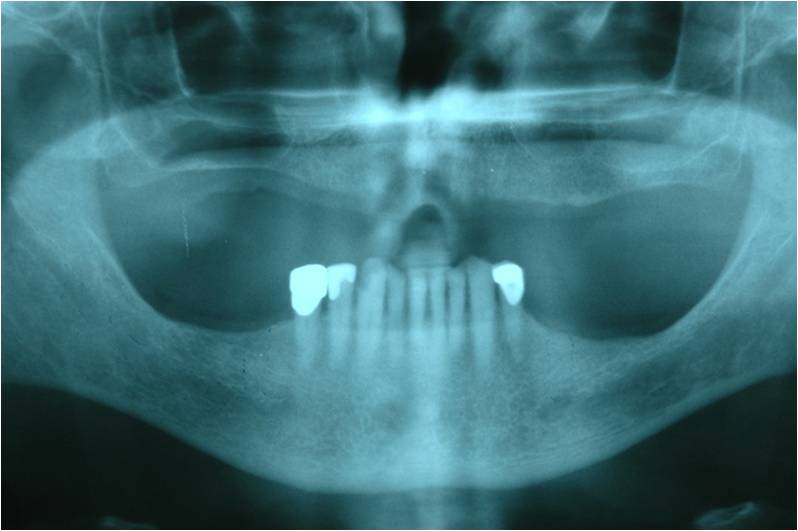

מקרה המתאר חוסר שיניים מוחלט בלסת עליונה.

עקב חוסר בעצם ואי רצון מצד המטופל לעבור הרמות סינוס בוצע תיכנון ממוחשב של מיקום השתלים עוד בטרם ההשתלה.